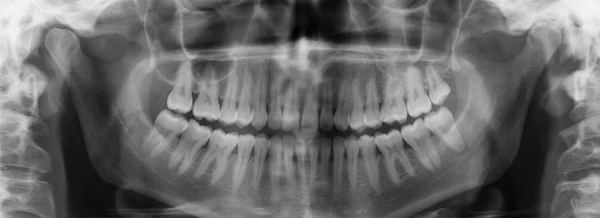

Panoramique dentaire (OPG)

La panoramique dentaire est un examen d’imagerie radiographique offrant une vue globale des dents, mâchoires et structures osseuses associées.